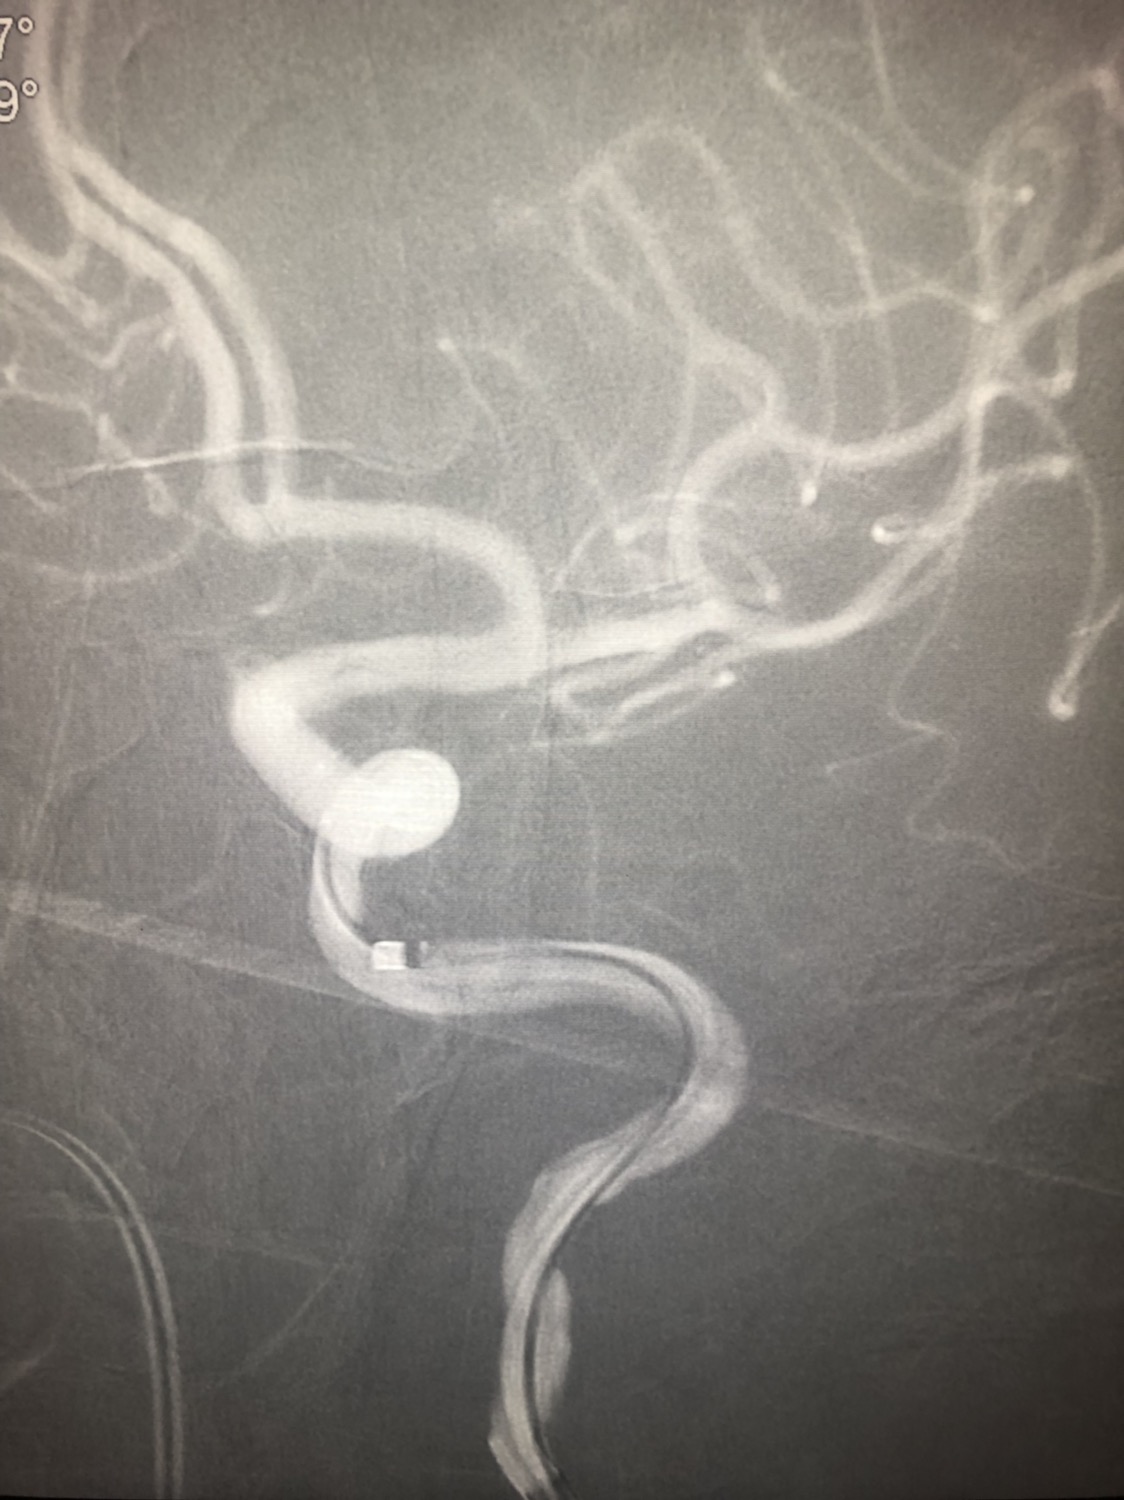

急诊二。zde,f53y。

意识模糊进行性加重8h,基底动脉闭塞,reco取栓再通,貌似动脉硬化,实际血管光滑。造影➕取栓8min。今日团队配合紧密,不到三小时全麻造影取栓带苏醒完成两台取栓。团队棒棒的!南阳市中心医院神经内科脑血管病介入团队